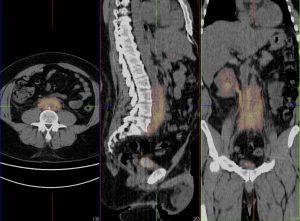

Fibrose rétro-péritonéale

Femme de 41 ans, récidive de douleurs abdominales 1 mois après l’arrêt de la corticothérapie chez une patiente suivie pour une fibrose rétro-péritonéale idiopathique.

Hypermétabolisme intense diffus en faveur d’une évolutivité de la fibrose rétro-péritonéale idiopathique connue.

A noter l’accumulation du radiotraceur aux niveaux des voies excrétrices urinaires proximales.

Traceur: 18-FDG